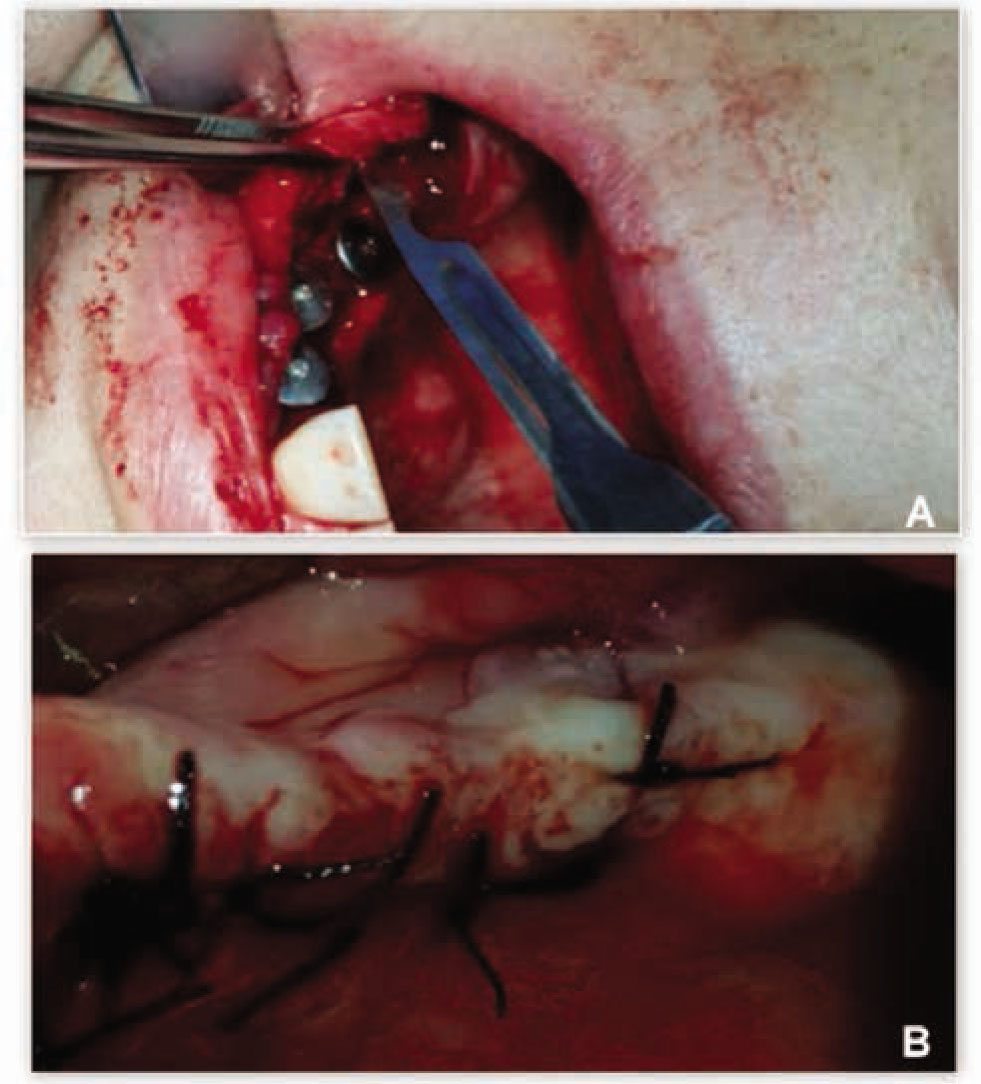

Figure 4 Clinical view of the final surgical steps performed in one patient treated with the new flapless split crest procedure combined with PRF.A: Implant insertion and flap release incision;B: Primary closure of the flap

Figure 4

Clinical view of the final surgical steps performed in one patient treated with the new flapless split crest procedure combined with PRF.

A: Implant insertion and flap release incision;

B: Primary closure of the flap